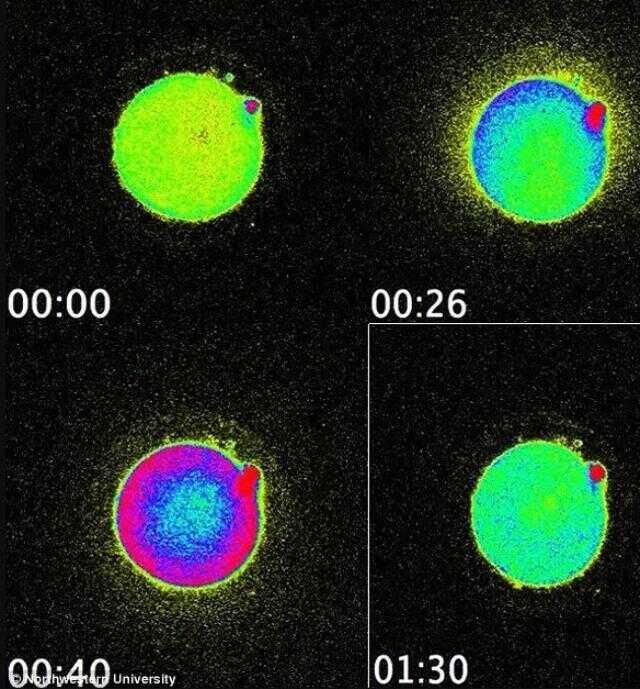

Mucizevi olay daha önce hayvanlarda gözlemlenmişti. Ancak bugüne kadar insanlardaki bu parıltıyı gözlemleyebilen olmamıştı. Bir şaşırtıcı şey ise bazı yumurtalar diğerlerinden daha fazla parlak parlıyor, bu da sağlıklı bir embriyo oluşturabilme konusundaki yeteneklerini gösteriyor.

Bu olayı nasıl kanıtlayacaklarını yıllarca düşünen bilim insanları 2014 yılında bu olayı ilk defa gözlemlemiş, ve sperm yumurtayı deldiği anda salgılanan serbest duruma geçen milyarlarca çinko atomunu seyretmişti.

Yeni bir flörasan algılayıcı kullanarak canlı hücrelerdeki çinko atomu hareketlerini takip eden bilim ekibi, yumurtadaki çinko depolama yeteneğini fark etti. Yaklaşık 8000 değişik küçük haznede depolanan 1 milyon civarında çinko atomu döllenme gerçekleşince havai fişek gibi ateşleniyor. Döllenmenin ardından 2 saat boyunca bu olay devam ediyor. Kaynak: Süperileri.com, Nature.com